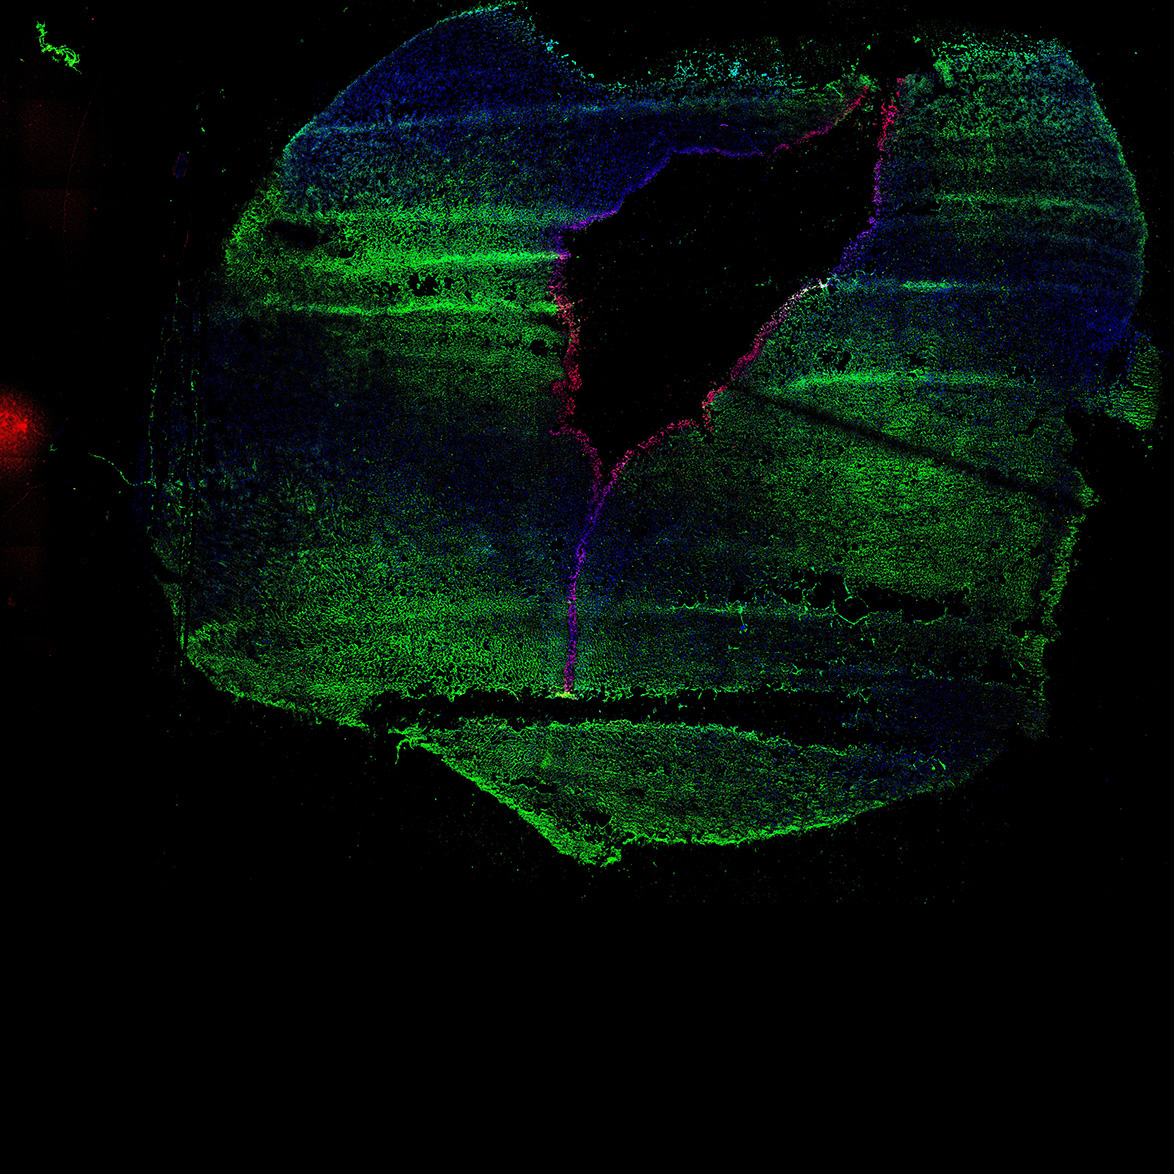

11PCW

DAPI

11PCW human midbrain

MAP2

SOX2

Merged

TH